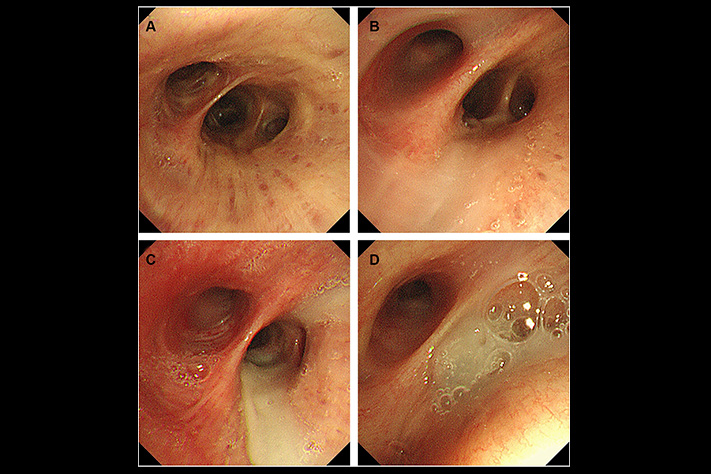

What they found: In every single patient's airways, there was a dense layer of mucus at the very bottom-below the fresh mucus, below where any treatment could reach.

The layer had been there for months. Sometimes over a year.

The cilia-those tiny hairs that sweep mucus out-were completely buried under it. Non-functional.

The researchers tested standard treatments on this bottom layer.

Nothing worked. Not Mucinex. Not saline nebulizers. Not NAC. Not any expectorant or supplement.

The molecular structure was different. Denser. Surface treatments couldn't break it down.

He showed her a diagram. "This is what you cough up every morning. Fresh mucus. Mucinex thins this. Your nebulizer helps with this."

Then he pointed lower. "But underneath, there's another layer. Old mucus. Months old, maybe years. Your cilia are buried under it."

"When you lie down, gravity shifts it up. Blocks your airway. That's why you wake up choking. That's why nothing you've tried has worked."

He pointed to the bottom layer again. "That's the difference. Everything you've tried works on what you can cough up. But this layer? It's too deep. Too hardened. Surface treatments can't touch it."